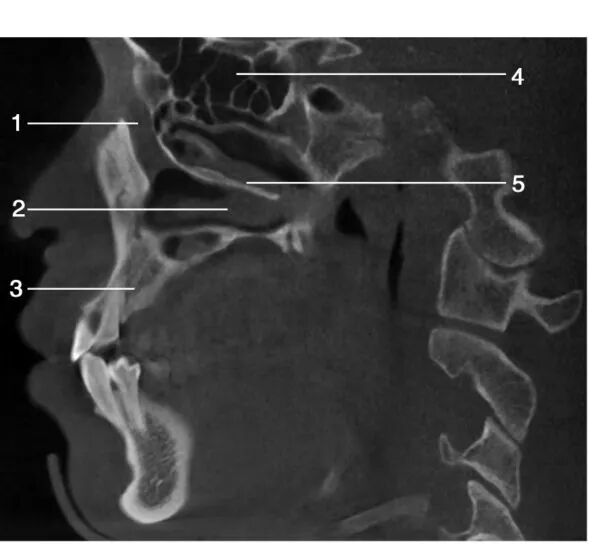

1.额骨( frontal bone) ; 2.鼻额缝( nasofrontal suture) ; 3.鼻骨( nasal bone) ; 4.硬腭( hard palate) ; 5.切牙管( incisive canal) ; 6.蝶窦( sphenoid sinus) ; 7.软腭( soft palate)